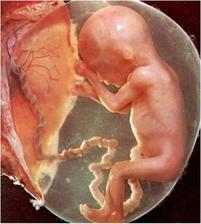

Jak asi víte, těhotenství je členěné na tři časové úseky, kterým říkáme trimestry – každý z nich trvá tři měsíce. Každý z trimestrů je zcela specifický, probíhají v něm určité charakteristické změny, podstupuje se vyšetření a nesou s sebou jiné pocity a obavy nastávající maminky.

V okamžiku zjištění těhotenství se žena ocitá na prahu zhruba čtyřicetitýdenní cesty. Někomu se zdá, že tato doba uteče jako voda, jindy je to vnímáno jako nekonečný proces. Každé těhotenství je individuální. Pro zdárný průběh těhotenství je důležitá tělesná a duševní pohoda.